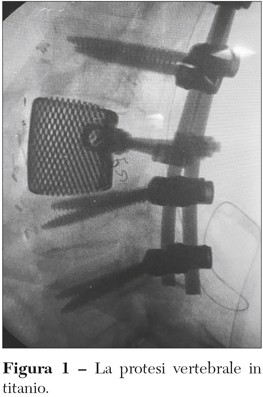

Recentemente, nella sua Unità Operativa è stato realizzato l’impianto di una vertebra in titanio stampata in 3D custom made. Ci può descrivere le ragioni di questa procedura e i costi necessari per attuarla?

La tecnologia 3D, introdotta nella pratica clinica da pochi anni, permette di ricostruire in modo anatomicamente perfetto e con materiale robusto, ultra leggero e poroso il segmento osseo che si vuole sostituire (Figura 1). La TC tridimensionale permette infatti una precisa progettazione della protesi e la costruzione con la stampante 3D è perfetta. Il materiale ultraleggero non più liscio ma poroso, consente, oltre al fissaggio meccanico, un definitivo ancoraggio biologico, ottimale anche per le parti molli. Partendo da una TC 3D, con aggiunta di piccoli segmenti metallici, si stampa un pezzo poroso in titanio che è la copia esatta della parte da sostituire. Di struttura porosa sono anche i fittoni, le viti e gli steli da inserire e questo consente all’osso di crescere intorno alla protesi così da ottenere, oltre alla solita fissazione meccanica, una fissazione biologica, perché le strutture ossee incorporano la protesi e anche le parti molli si ancorano meglio. Le protesi 3D vengono usate soprattutto nei tumori di bacino, vertebre e scapola, ove non esistono protesi modulari (Figura 2). Oggi, dato che è in aumento la necessità di sostituire vecchie protesi d’anca che si sono usurate nel tempo, si usano anche per questa patologia benigna. Quanto ai costi, le protesi in 3D variano dagli 8.000 ai 12.000 euro. Anche se un po’ alti, rimangono comunque nei parametri standard. La Regione indirà presto una gara per le ditte che producono le protesi custom made e i costi dovrebbero diminuire.